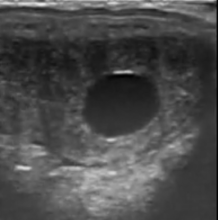

Der Tierarzt führt eine vollständige klinische und sonographische Untersuchung der Schlüsselstrukturen durch:

• Eierstöcke: Überwachung der Follikeldynamik zur Vorhersage des Eisprungs und zur Erkennung funktioneller Anomalien (persistierende Gelbkörper, Zysten).

• Gebärmutter: Kontrolle des Tonus und der Gebärmutterumgebung. Besonderes Augenmerk legen wir auf das Fehlen übermäßiger postovulatorischer Ödeme oder Endometritis, die Hauptfaktoren für frühe Resorptionen sind.